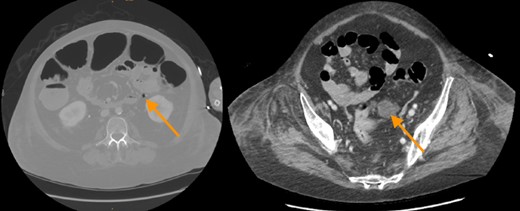

A 49-year-old woman required urgent osteosynthesis of a periprothetic femur fracture after trauma to the left hip. Due to long standing (~48 y) rheumatoid arthritis the patient was immunosuppressed with corticosteroids and adalimumab and had underwent multiple joint replacements since her childhood. At the third postoperative day after osteosynthesis of the fractured femur she suffered from large bilateral pulmonary embolism at the orthopedic patient-department. Two days later septic shock had developed, apparently from a necrotizing fasciitis of the leg. The perioperative antibiotic treatment with clindamycin was extended empirically with cefeprime and fosfomycine. A whole-body scan was performed which revealed free gas in the retroperitoneum as a sign of a covered perforated diverticulitis (Fig. 1). Due to increased systemic infection signs (CRP, elevated WBC, PTC) and life-threatening patient's condition a multidisciplinary decision was made to first treat the necrotizing fasciitis. Immediate debridement of the necrotic tissue, including the subcutaneous tissue to the fascia of the leg, was performed by plastic surgeons (Fig. 2). Postoperatively multiple organ dysfunction developed, including acute lung failure, the patient required veno-venous extracorporeal membrane oxygenation (vvECMO).

CT-scan revealed free gas and fluid in the retroperitoneum as a sign of a covered perforation of colonic diverticula.